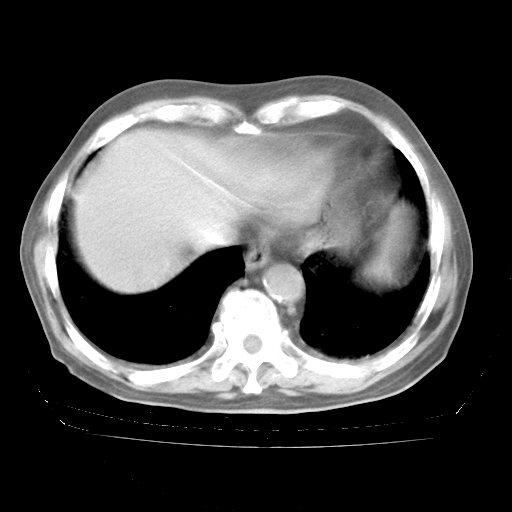

4月28日肺部CT——再次出现类似去年5月9日——透光度降低,“间质性”改变。

4月28日肺部CT——再次出现类似去年5月9日——磨玻璃样、间有“粟粒样”改变。

4月28日肺部CT